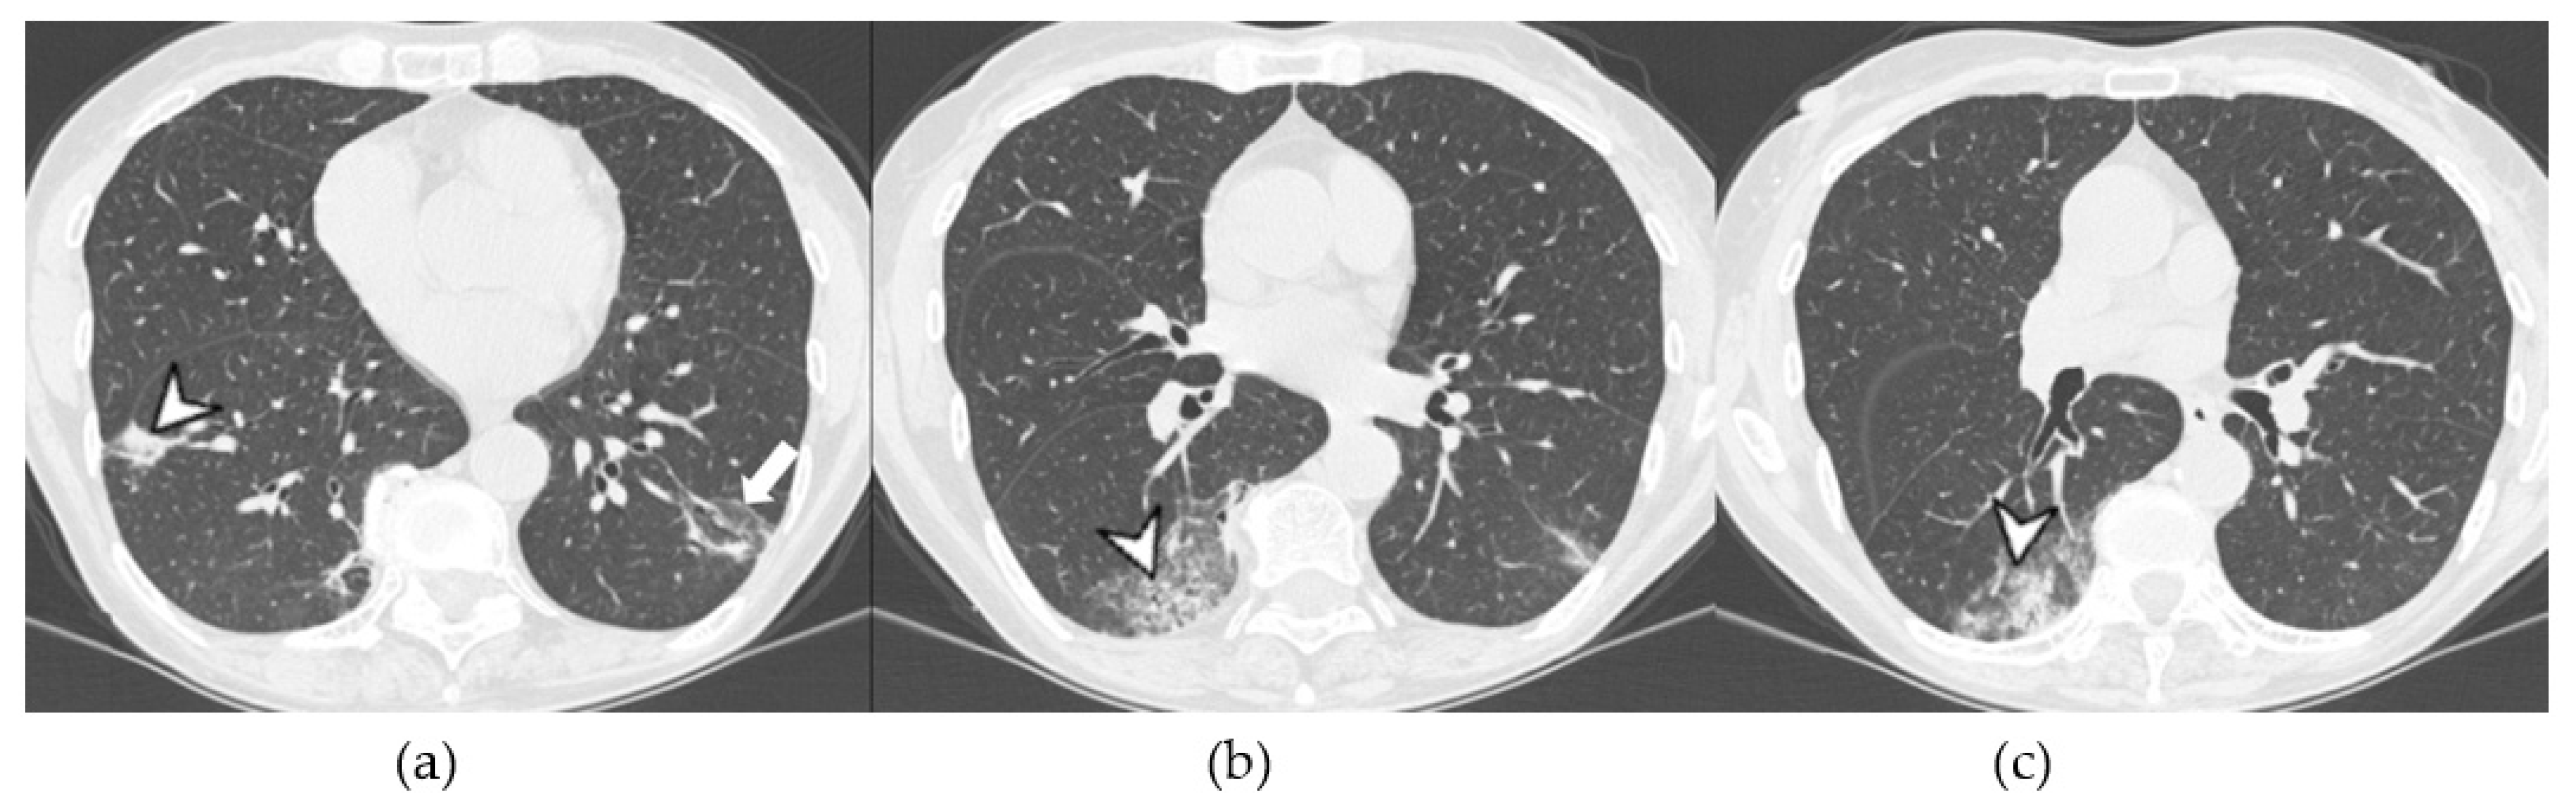

4.2.2. HRCT Findings of Patients with Anti-MDA-5 Abs

| Lesions | GGO, reticulations, consolidations | consolidations, GGOs | |

| Distribution | Homogeneous; lower lung lobes, along bronchovascular bundles and lung periphery; loss of volume of lower lobes | Patchy; peripheral lower lobes or along the bronchovascular bundles | |

| CT pattern | NSIP OP NSIP-OP UIP DAD-unclassifiable | 50% 20% 25% 10% +/− | 20% 50% 25% <5% ++ |